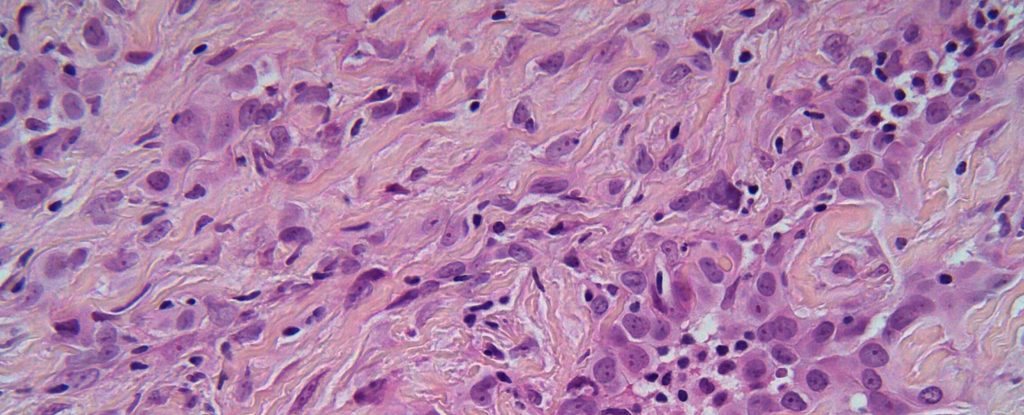

Dobbelt immunterapi forlænger fortsat overlevelsen ved malignt pleural mesotheliom

CheckMate 743-studiet tyder på, at immunterapi-kombinationen nivolumab + ipilimumab er vejen til overlevelse hos patienter med inoperabel malignt pleural mesotheliom.